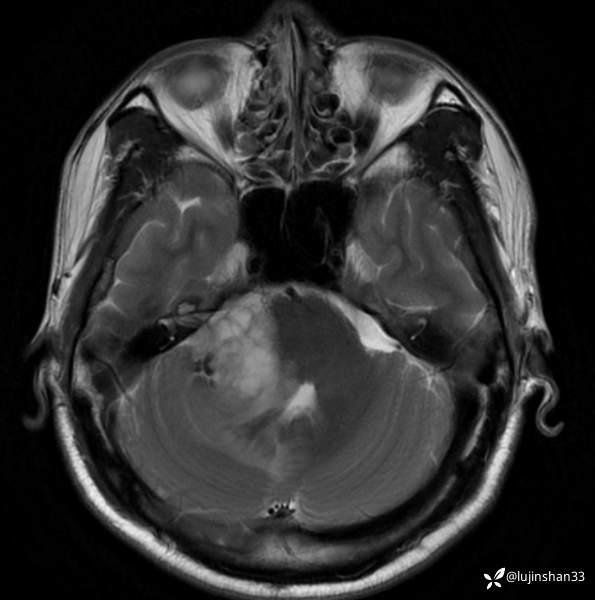

术前CT及MRI

临床诊断:右侧桥小脑角血管母细胞瘤

讨论:桥小脑角区占位,血供情况如何判定?良恶性如何从影像学判定?